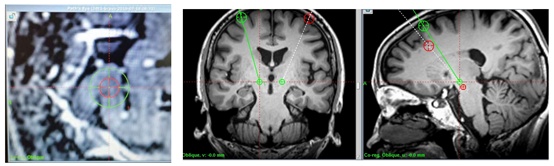

6月10日,在神经内科主任汪昕教授、神经外科主任张晓彪主任医师的指导与麻醉、护理团队的通力协作下,由神经外科朱卫副主任医师、孙崇璟医生和神经内科金莉蓉主任医师为其进行了DBS手术,手术运用国产脑起搏器,将小电极精准定位、插入至相应的大脑核团,并将其连接于放置在胸部的脉冲仪,通过控制电流刺激电极传递到大脑深处,激活平衡大脑。4小时后,手术顺利完成,术后李先生行动迟缓、僵硬和震颤的症状明显改善,维持效果从短短几小时延长到了一整天,恢复了正常生活。

DBS手术,又称脑起搏器植入术,是将电极精准植入到患者脑内的丘脑底核或苍白球内侧部等区域,发出弱电脉冲,抑制引起帕金森病症状的异常脑神经信号,从而改善帕金森病的肌肉震颤、僵直、运动启动困难、姿势反射异常等症状。当前,DBS手术是是治疗帕金森病的重要手段,相对于药物治疗,其疗效更为稳定,因此DBS可在患者药物无效期起到主要缓解患者症状的作用。